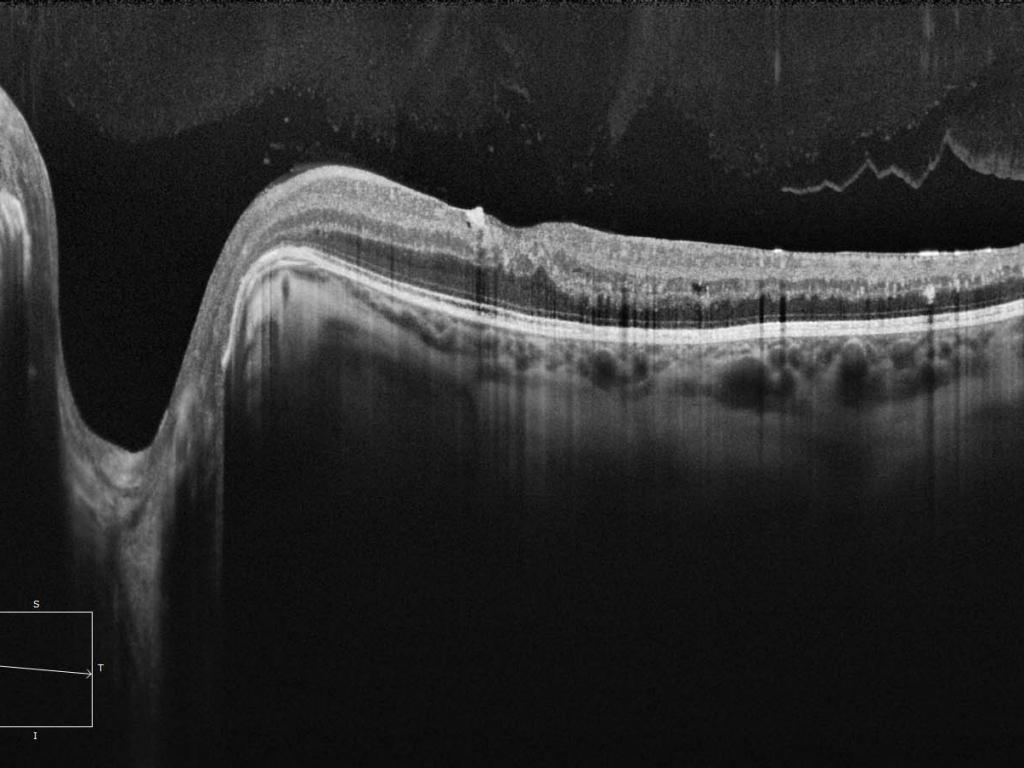

We begin with a full diagnostic exam using premium ZEISS technology.

Your cornea shape, cornea thickness, retina, optic nerve, dryness level, and overall eye health are scanned in detail.